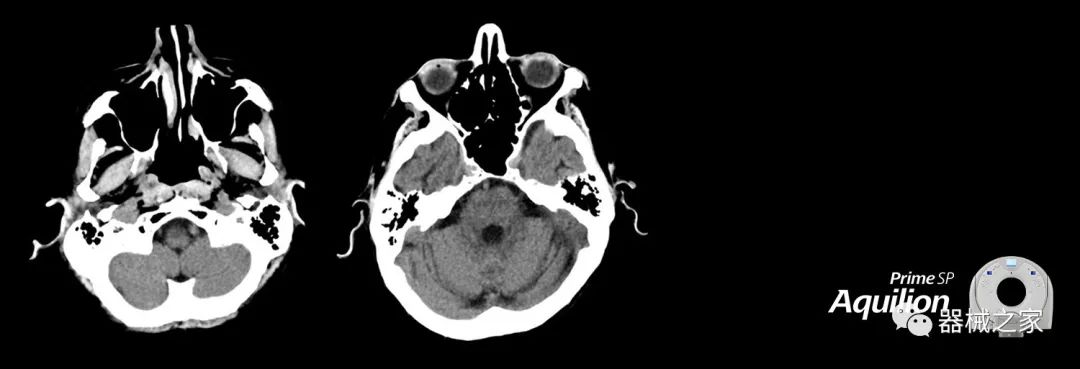

在以患者為中心的放射腫瘤學(xué)領(lǐng)域,計算機斷層掃描(CT)的可訪問性,可重復(fù)性和靈活性至關(guān)重要。為了建立這些價值,佳能醫(yī)療系統(tǒng)美國公司現(xiàn)在正在擴大其放射腫瘤學(xué)CT模擬產(chǎn)品,包括Aquilion Prime SP和Aquilion Lightning 80高級CT系統(tǒng)。除了Aquilion LB之外,Aquilion Prime SP和Aquilion Lightning 80現(xiàn)在還包括放射治療(RT)選項,可為腫瘤學(xué)規(guī)劃提供高質(zhì)量的CT成像和精密工具。

Aquilion Prime SP使設(shè)施能夠處理具有挑戰(zhàn)性的案例,同時為員工提供快速,靈活和高效的解決方案。

兩個CT系統(tǒng)均采用0.5 mm x 80排PUREViSION探測器技術(shù)(可配置并從80-160現(xiàn)場升級),78 cm孔徑,50 cm視野,AIDR(自適應(yīng)迭代劑量減少)3-D和SEMAR(單個)能量金屬神器減少)技術(shù)。